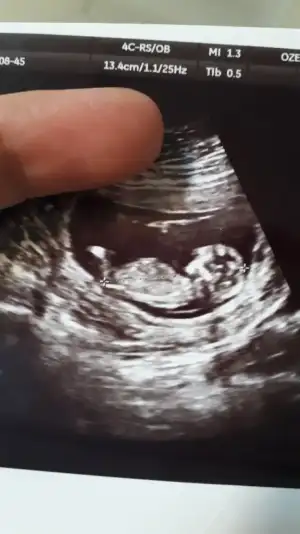

Bizde tahmin alabilir miyiz 13+2

• IMG_20190808_111703.webp

IMG_20190808_111703.webp

31,6 KB · Görüntüleme: 60